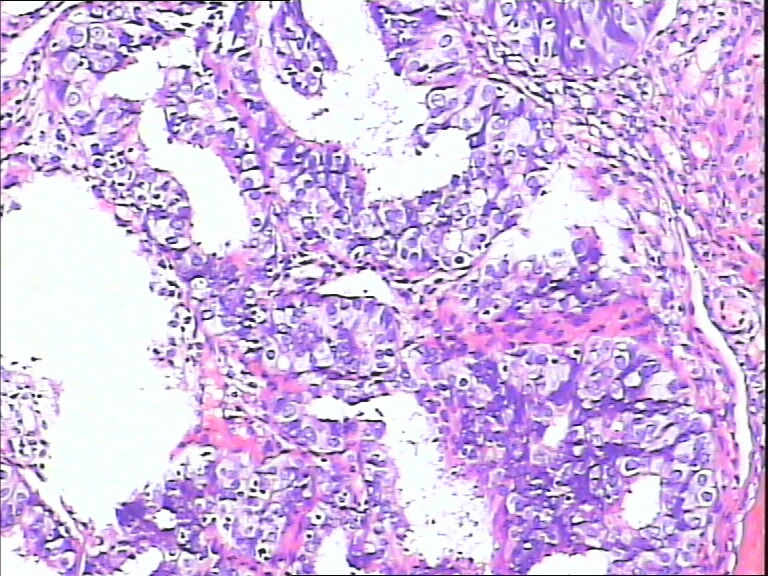

女,43y

左输卵管积液

输卵管长4.5cm;直径:0.8cm

• 请教:输卵管!图4

图4

输卵管增生性上皮病变。

慢性炎伴上皮增生

良性,炎症改变

考虑炎症